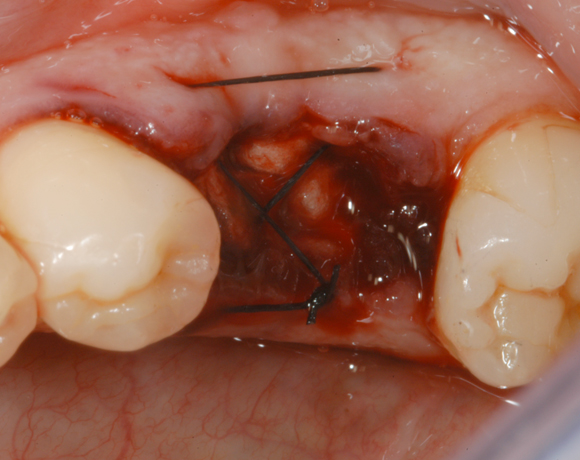

Im vorliegenden Patientenfall wurde eine große Extractionswunde mit einem Remotis® Cone und abschließend mit einem Remotis® Fleece versorgt

Bild 05: Kreutzstich Naht